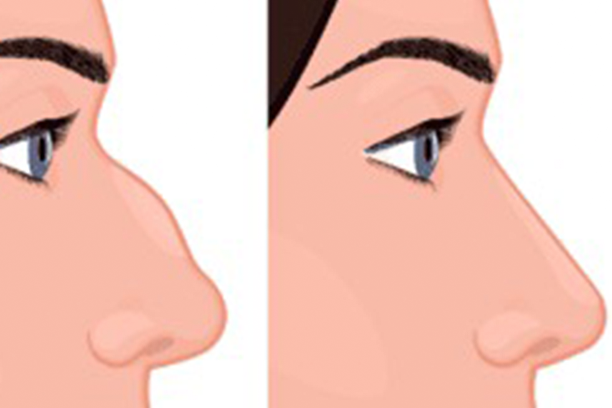

What Does Rhinoplasty Do?

Corrects Cosmetic Issues:

- Nasal Bridge Irregularities: Smooths dips, bumps, or irregularities.